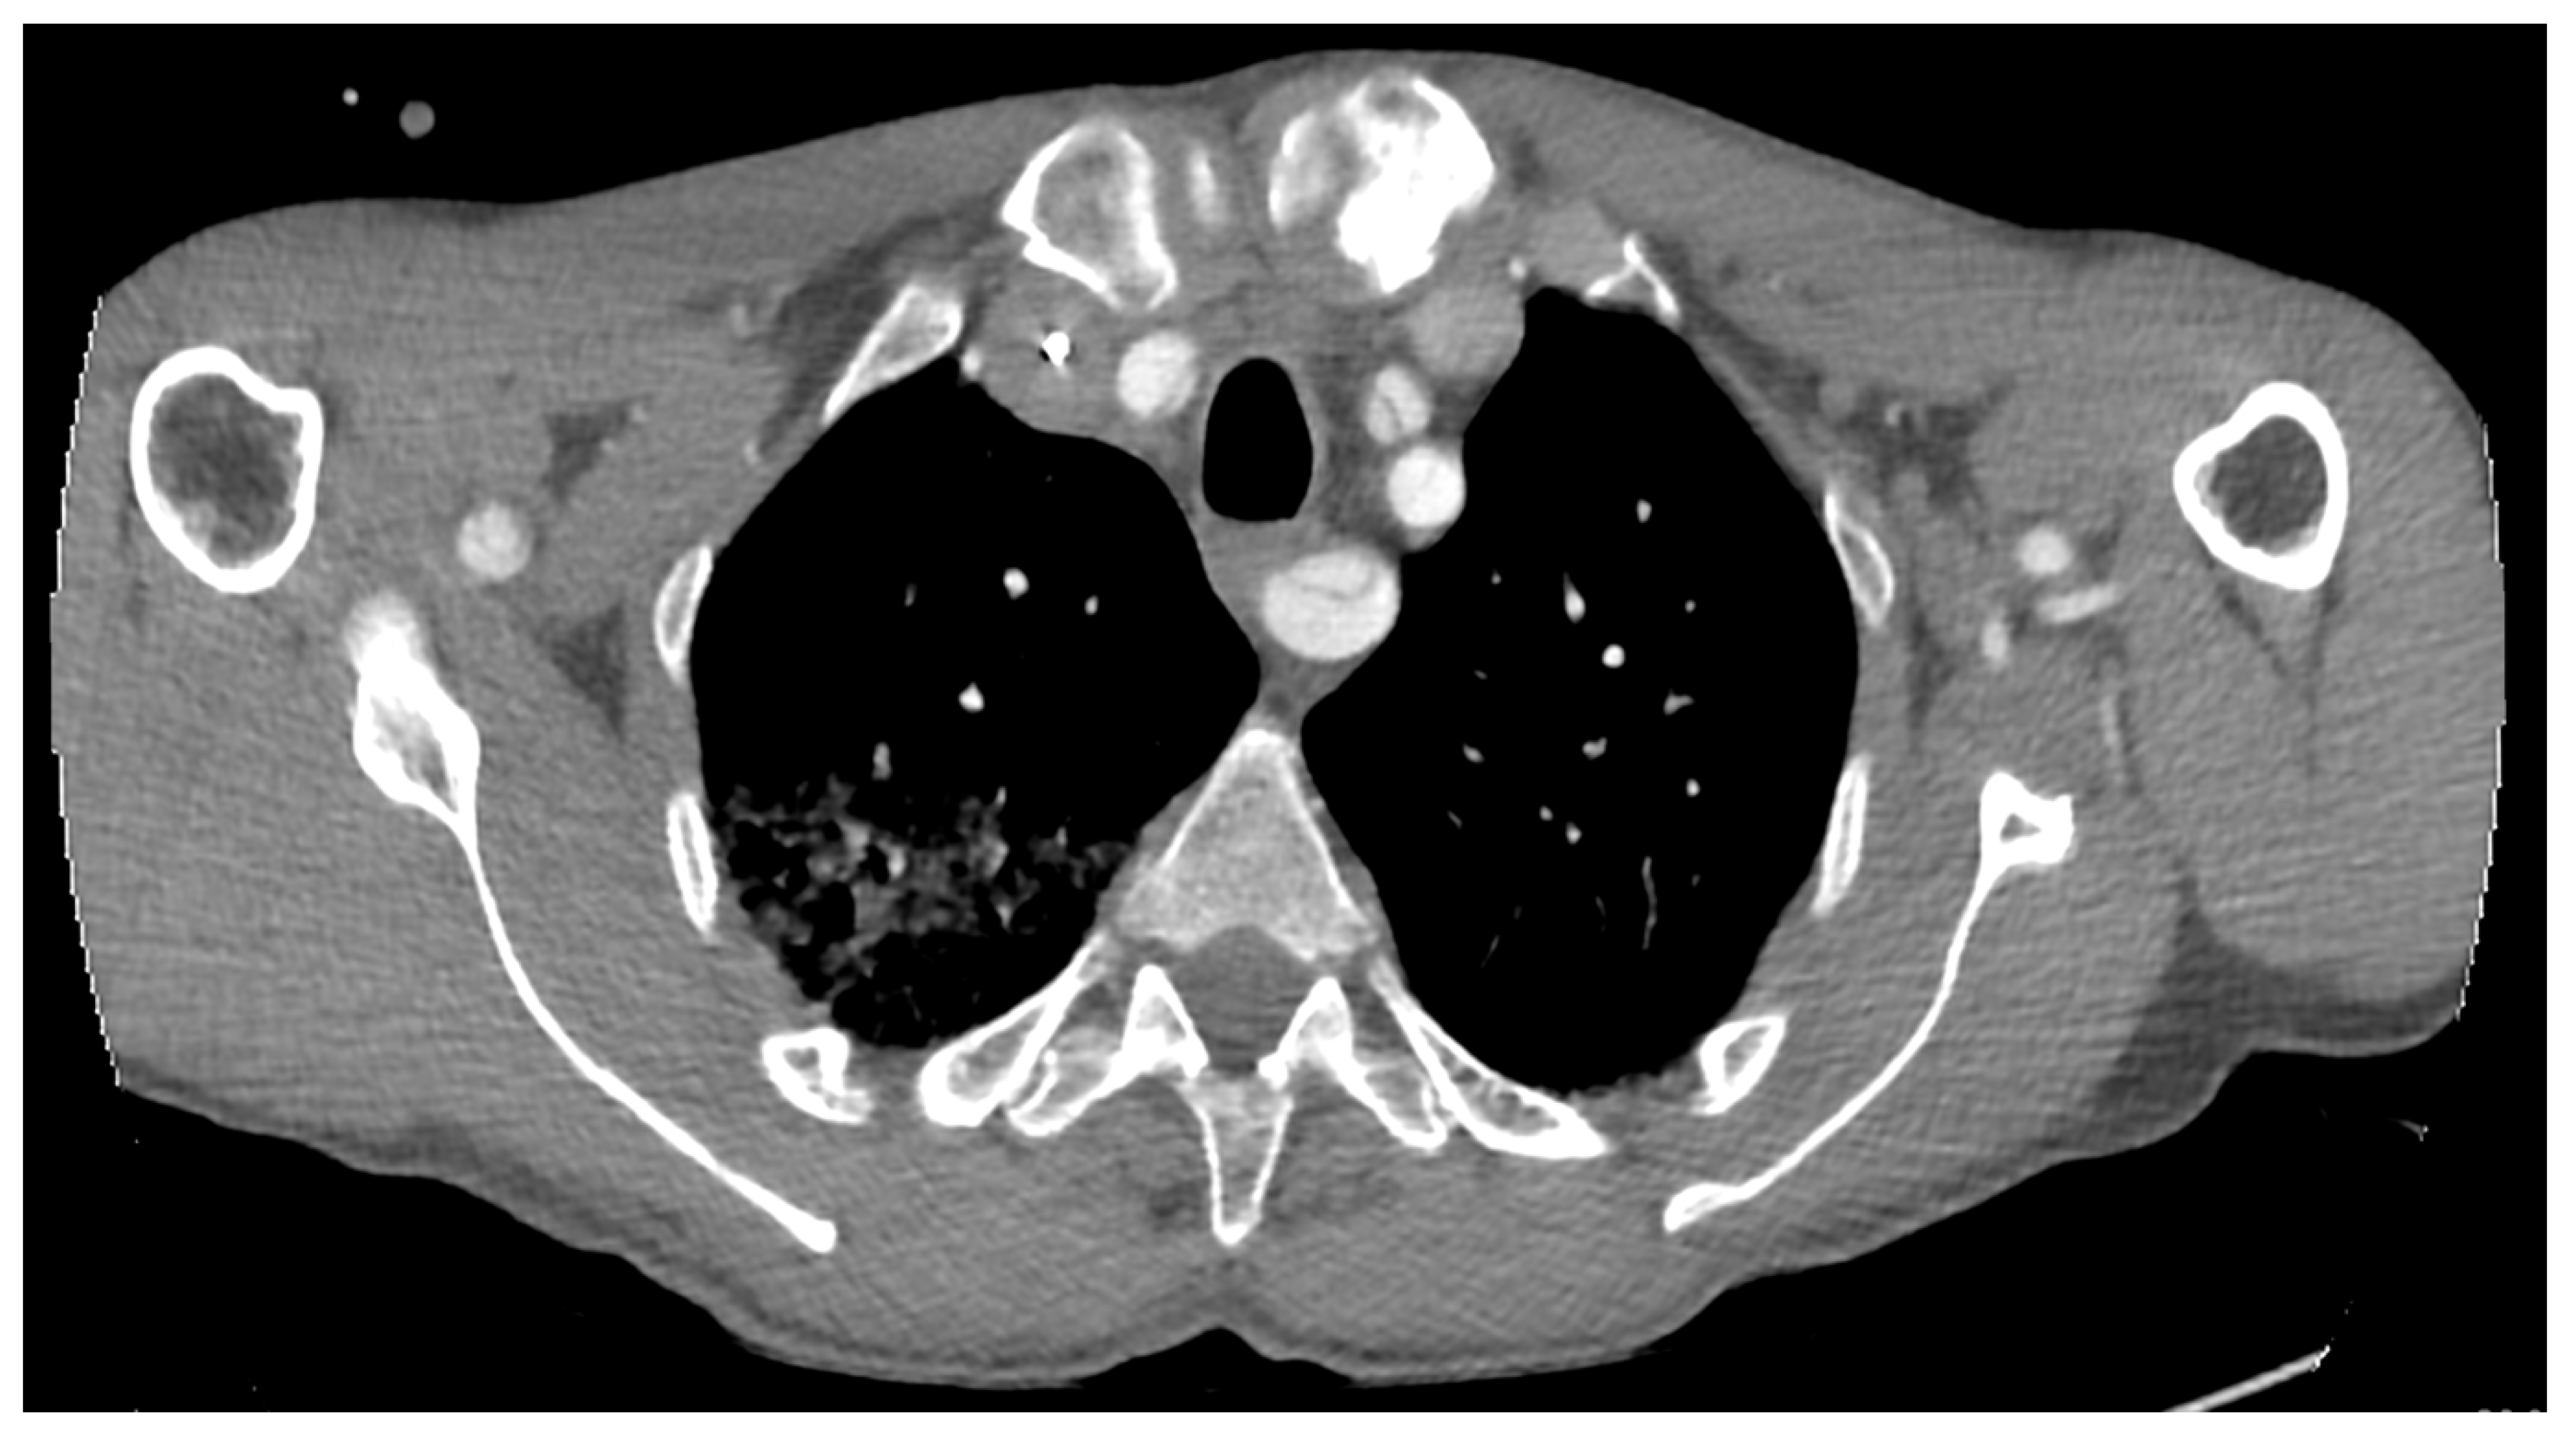

2. Case Report